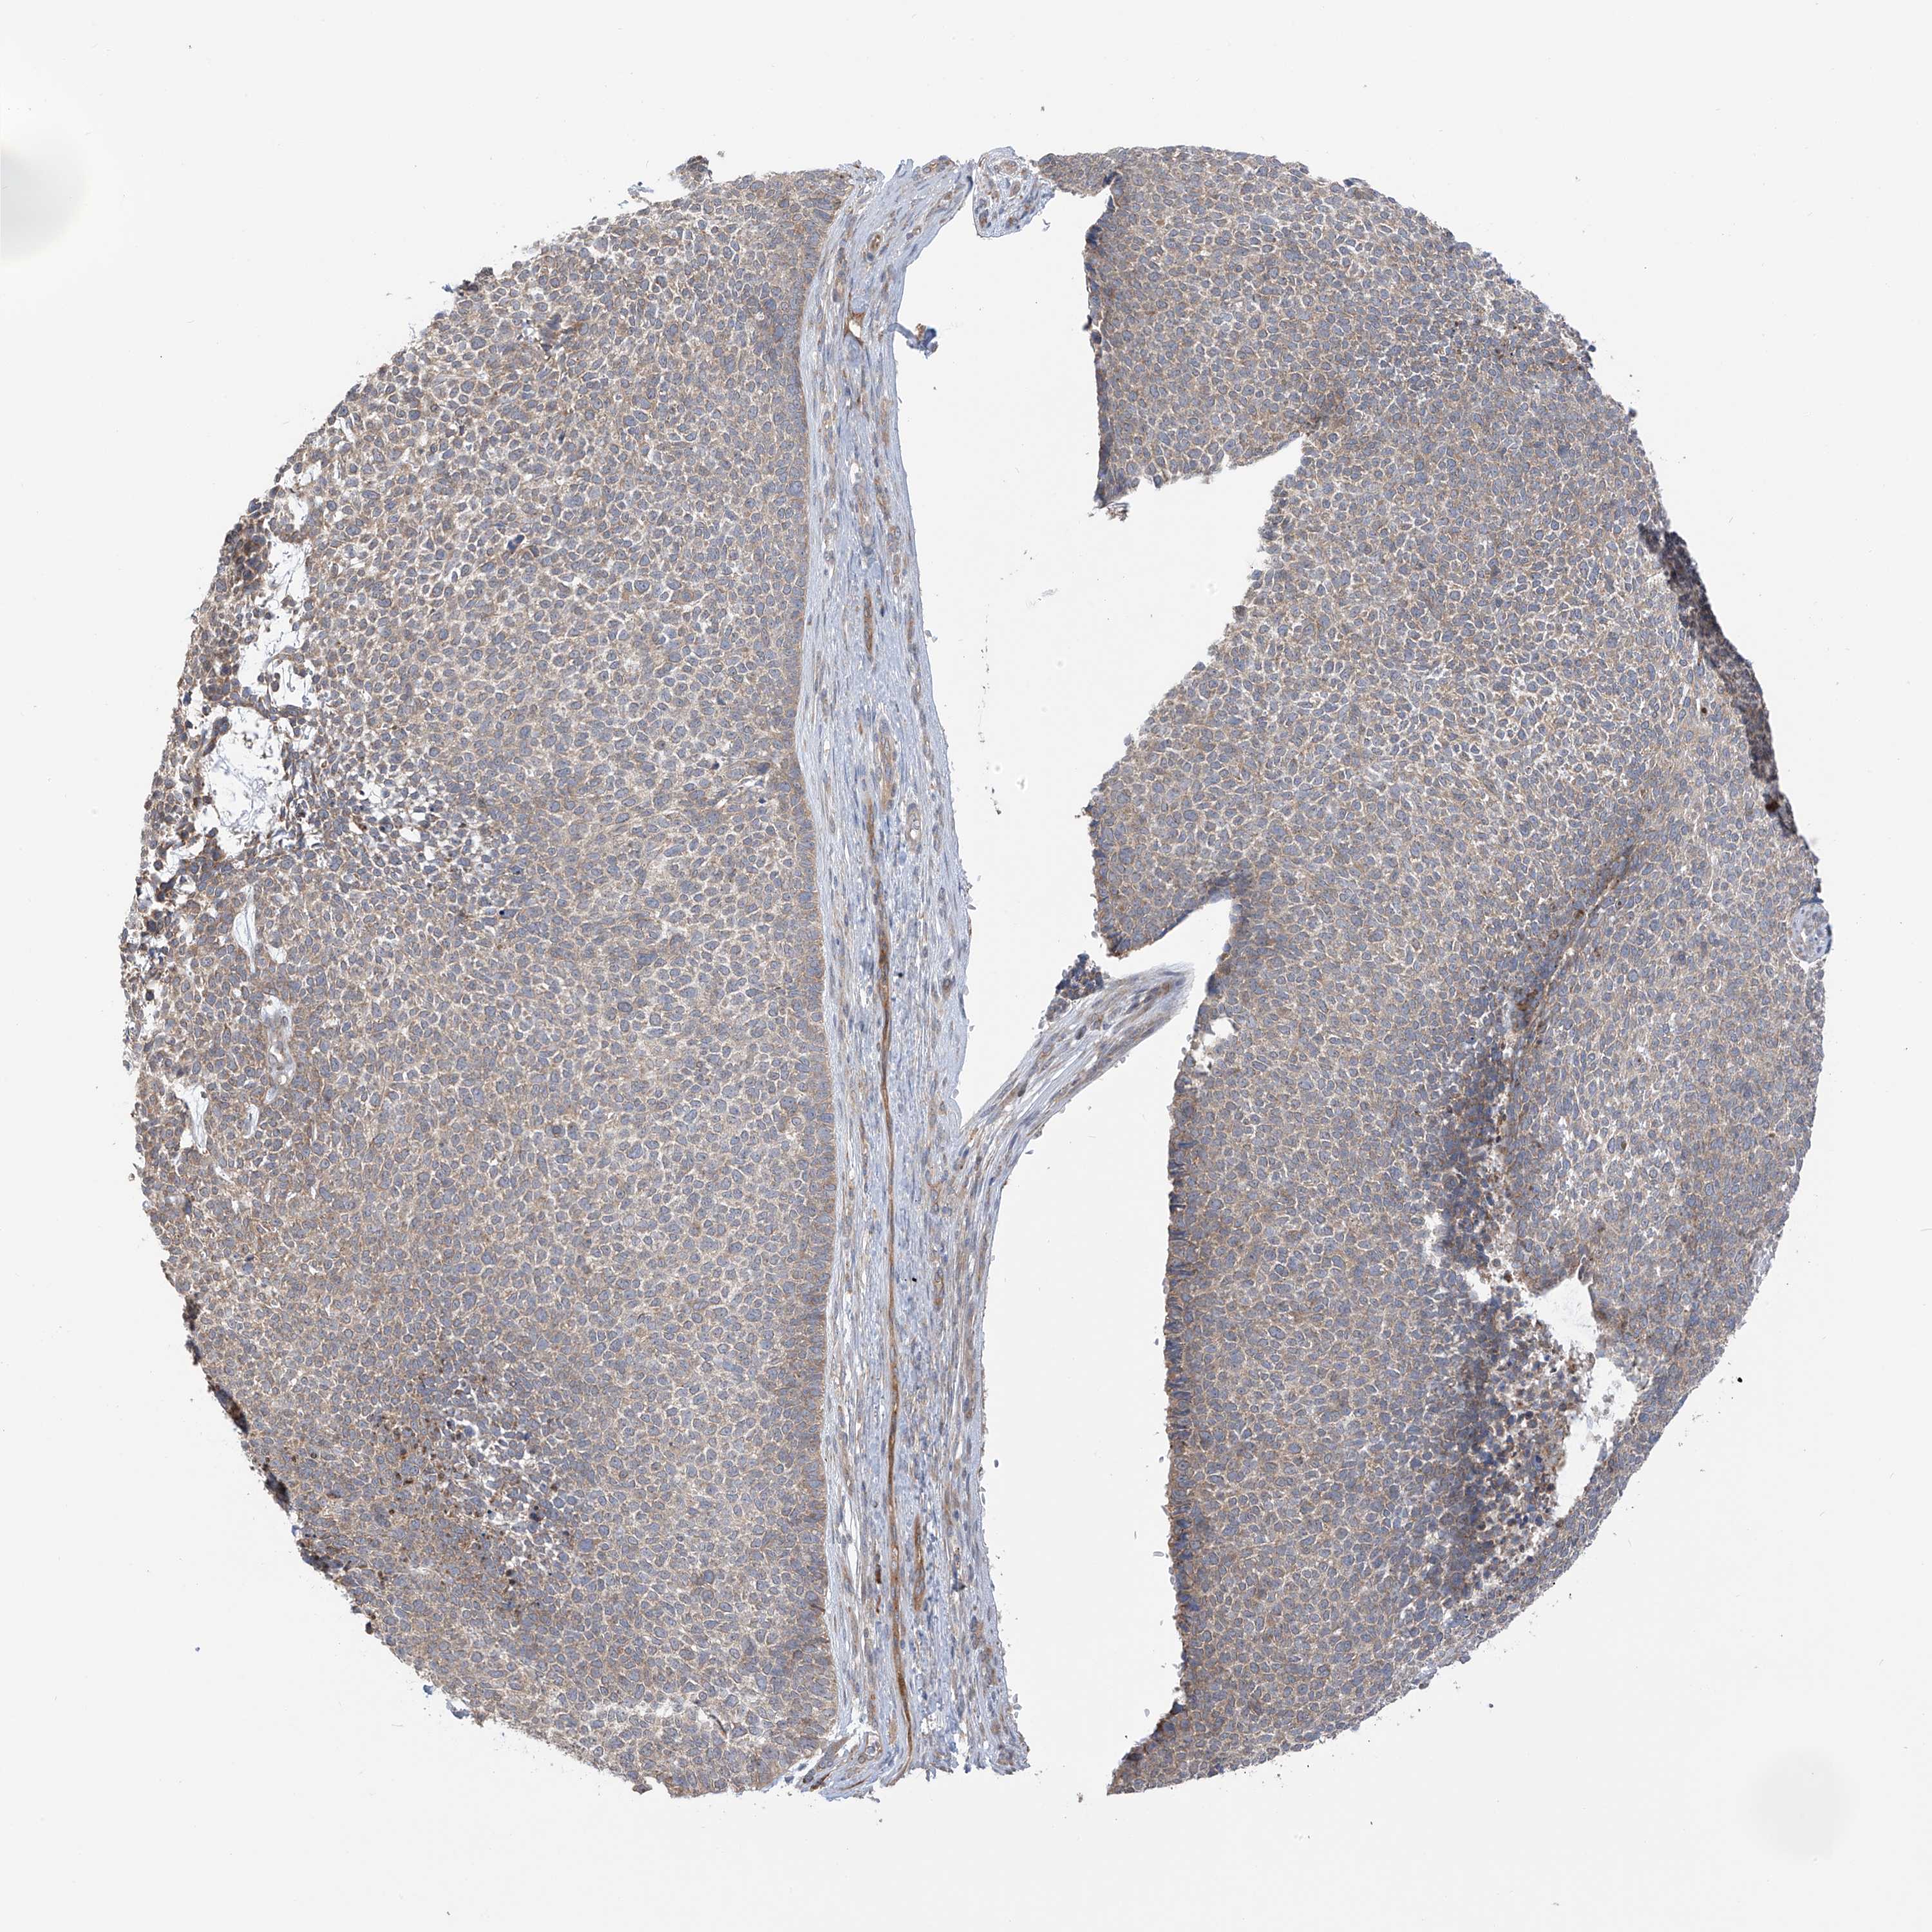

CANCER SKIN CANCER Show tissue menu

Basal cell and squamous cell cancer

SKIN CANCER - Protein expressioni

A mouse-over function shows sample information and annotation data. Click on an image to view it in a full screen mode. Samples can be filtered based on level of antibody staining by selecting one or several of the following categories: high, medium, low and not detected. The assay and annotation is described here.

Each image is clickable and will lead to virtual microscopy that enables deeper exploration of all samples and also displays staining intensity scores, fraction scores and subcellular localization as well as patient and tissue information for each sample.

Antibody HPA032050

Basal cell carcinoma

Squamous cell carcinoma, NOS

Squamous cell carcinoma, metastatic, NOS